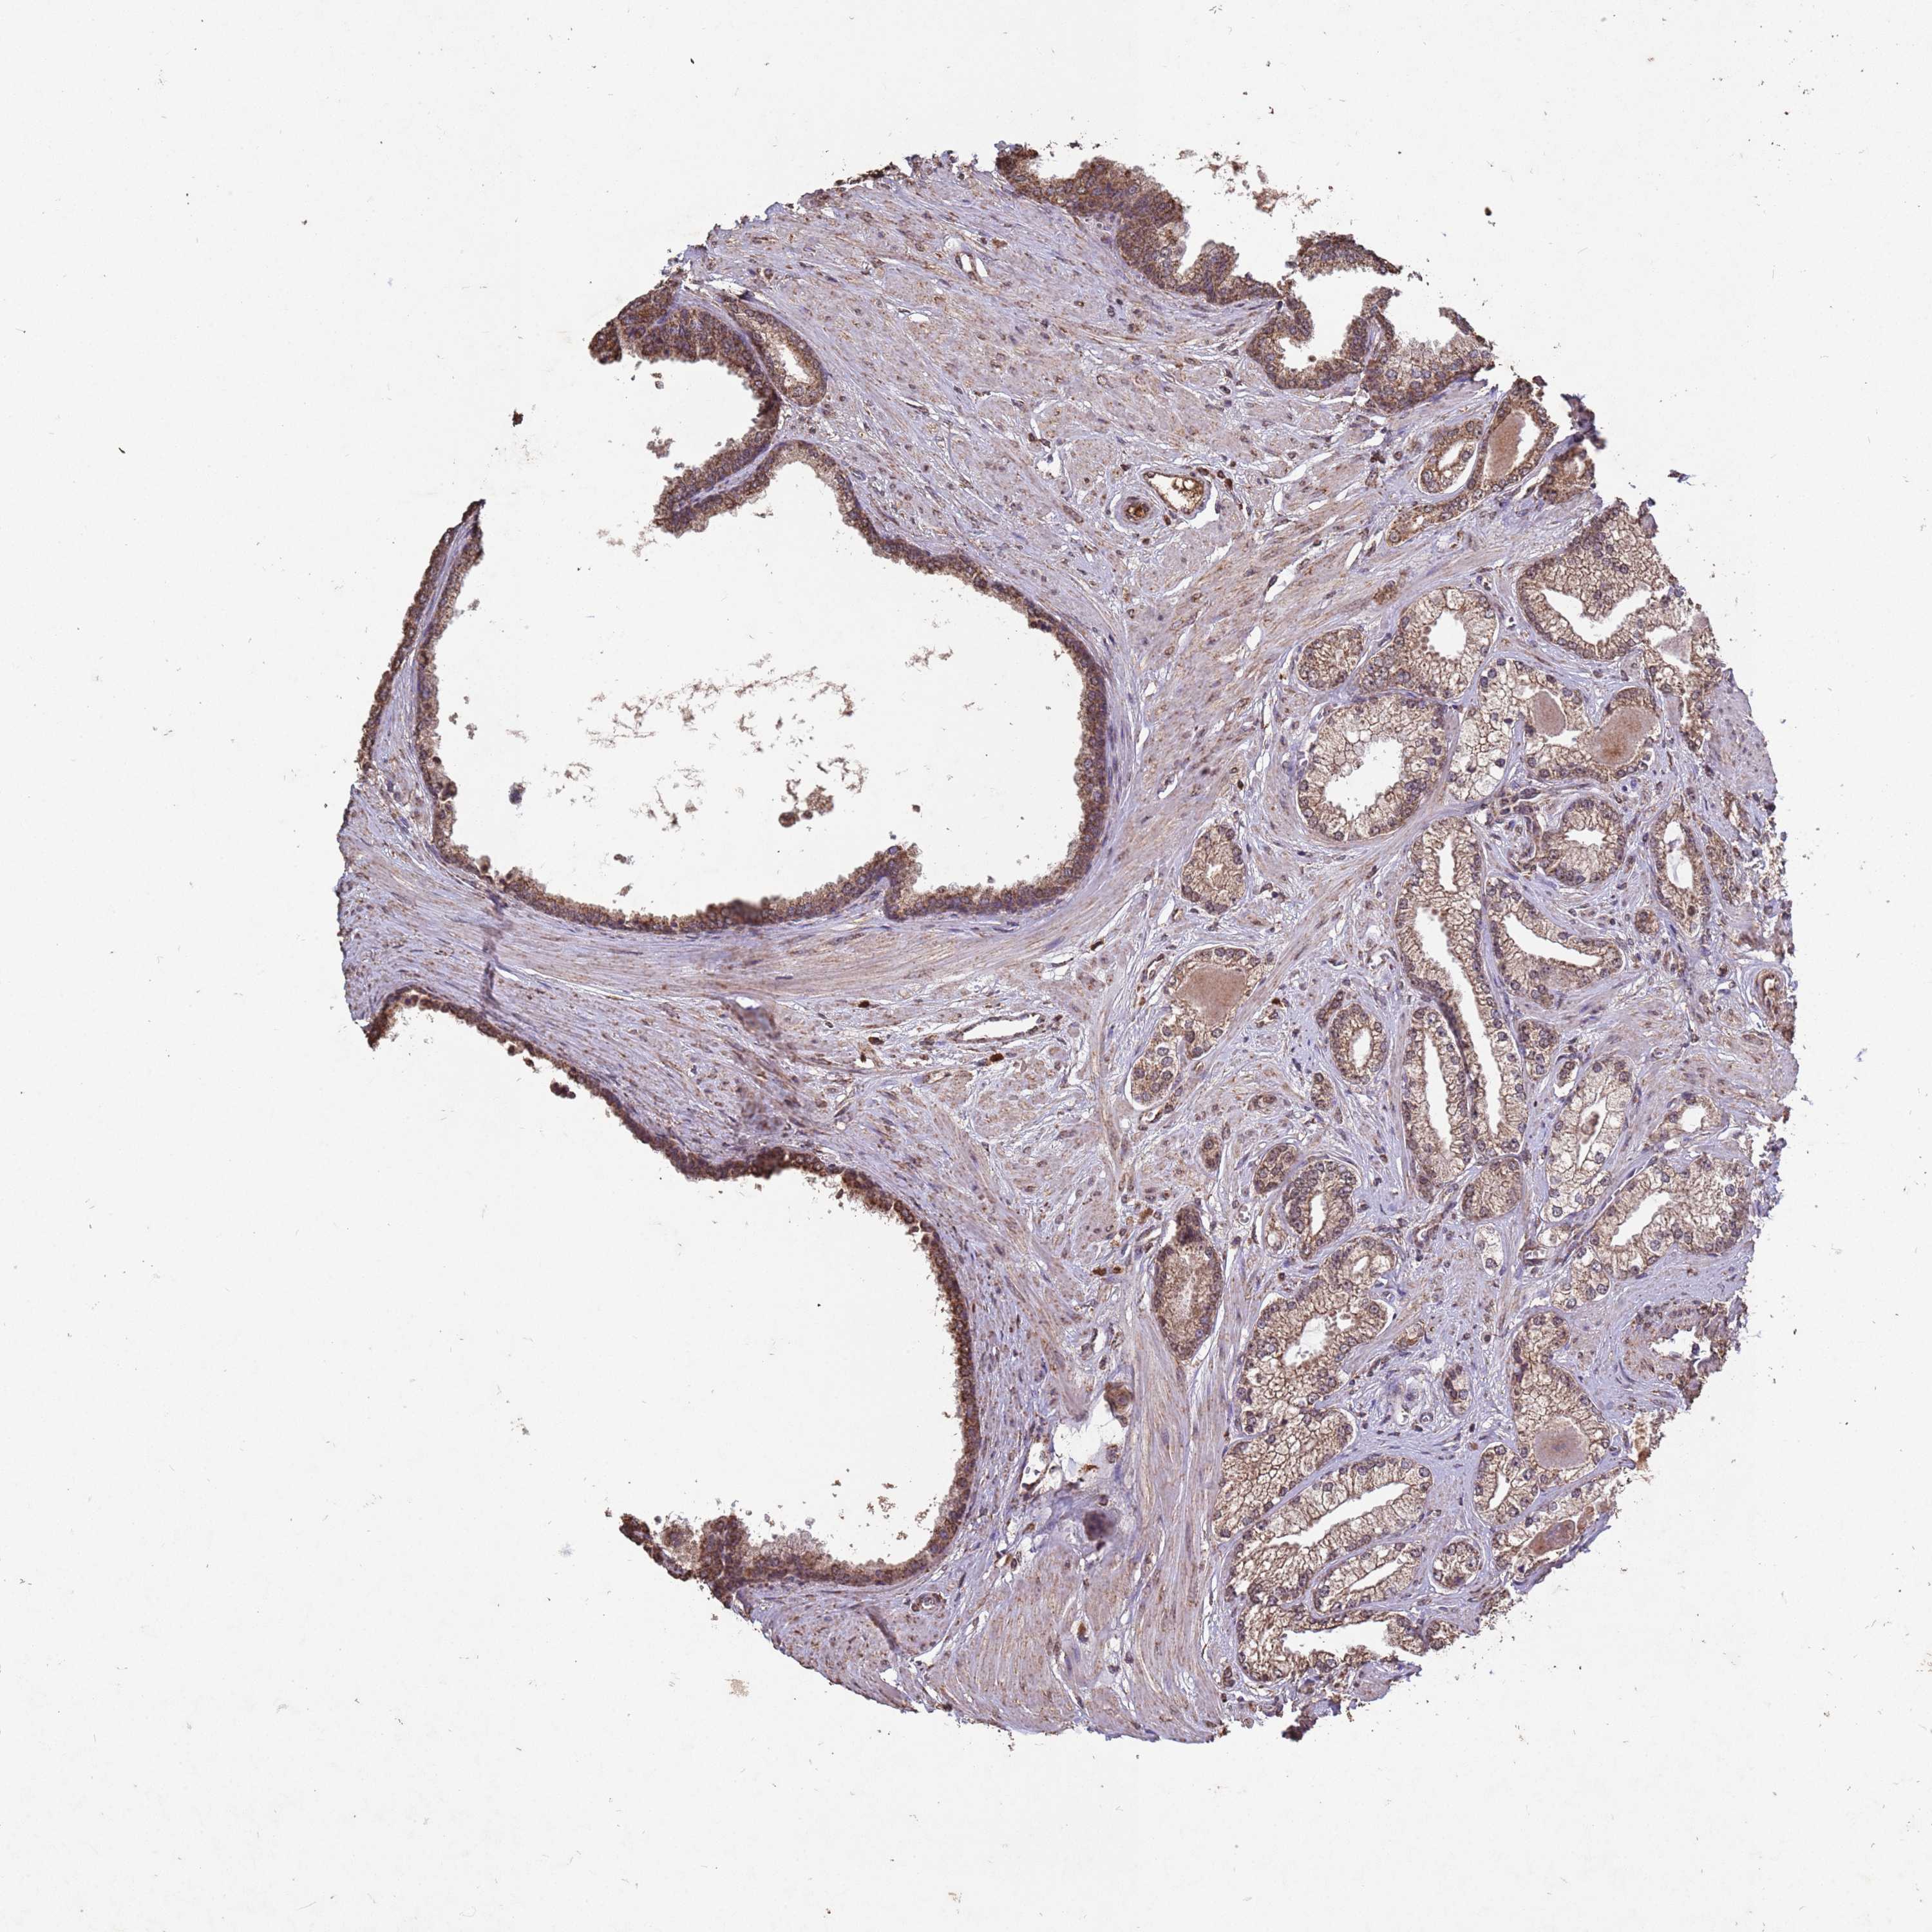

PROSTATE CANCER - Protein expressioni

A mouse-over function shows sample information and annotation data. Click on an image to view it in a full screen mode. Samples can be filtered based on level of antibody staining by selecting one or several of the following categories: high, medium, low and not detected. The assay and annotation is described here.

Antibody stainingi

Antibody staining in the annotated cell types in the current human tissue is reported as not detected, low, medium, or high, based on conventional immunohistochemistry profiling in selected tissues. This score is based on the combination of the staining intensity and fraction of stained cells.

Each image is clickable and will lead to virtual microscopy that enables deeper exploration of all samples and also displays staining intensity scores, fraction scores and subcellular localization as well as patient and tissue information for each sample.

Antibody CAB045977

Staining

High

Medium

Low

Not detected

Intensity

Strong

Moderate

Weak

Negative

Quantity

>75%

75%-25%

<25%

None

Location

Nuclear

Cytoplasmic/membranous

Cytoplasmic/membranous,nuclear

Adenocarcinoma, High grade

Adenocarcinoma, NOS

Adenocarcinoma, Low grade